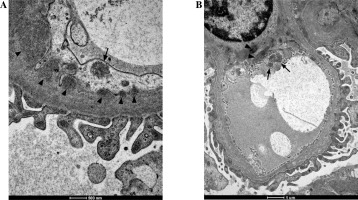

The evaluation of the biopsy samples in a light microscope revealed class III LN in five cases (50%), class II in three cases (30%), and class IV and class V in two individual cases (Table 1). Ultrastructural analysis of the biopsy material showed the presence of TRIs in seven patients (Table 3). These structures were most often found in endothelial cells of both the vascular bundle and the peritubular capillaries. They were occasionally observed in monocytes within capillaries and mesangial fields (Fig. 1). TRIs occurred within the irregularly widened cisterns of the endoplasmic reticulum. Some of them presented signs of pronounced swelling, which led to disruption of the surrounding membranes. In some inclusions, the tubular structures came into close contact with the membranes of the endoplasmic reticulum (Fig. 2). Both the size of the inclusions and the frequency of their occurrence varied among specimens (Fig. 3). The size of the TRIs varied in the range 300-1600 nm. Numerous TRIs (several inclusions in one glomerulus) were found in the biopsy of a patient with class V LN. All patients were tested for the most common viral infections connected with presence of TRIs (HIV, HBV, HCV, EBV, CMV) and all those disorders were excluded by performing simple blood tests. Only in one patient, after three years of treatment, was the re-biopsy performed. TRIs were still present in the specimen, but they were much less abundant (Fig. 4). In three cases with the highest presence of TRIs, the disease began before puberty (at 8-10 years of age), and in all these cases hematological disorders such as leukopenia, anemia, and thrombocytopenia preceded the LN diagnosis. Inclusions in a typical location, near subendothelial deposits, were observed in only one patient (Fig. 5). Biopsies of three patients with disease onset in adolescence (around 14 years of age) revealed no TRIs in the sampled material. In these patients, arthritis and nephrotic proteinuria dominated the clinical picture.

Fig. 1

Tubuloreticular inclusions (TRIs) observed in monocytes (A) and macrophages (B) in renal biopsy samples collected from patients with juvenile systemic lupus erythematosus (jSLE). TRIs are indicated with arrows